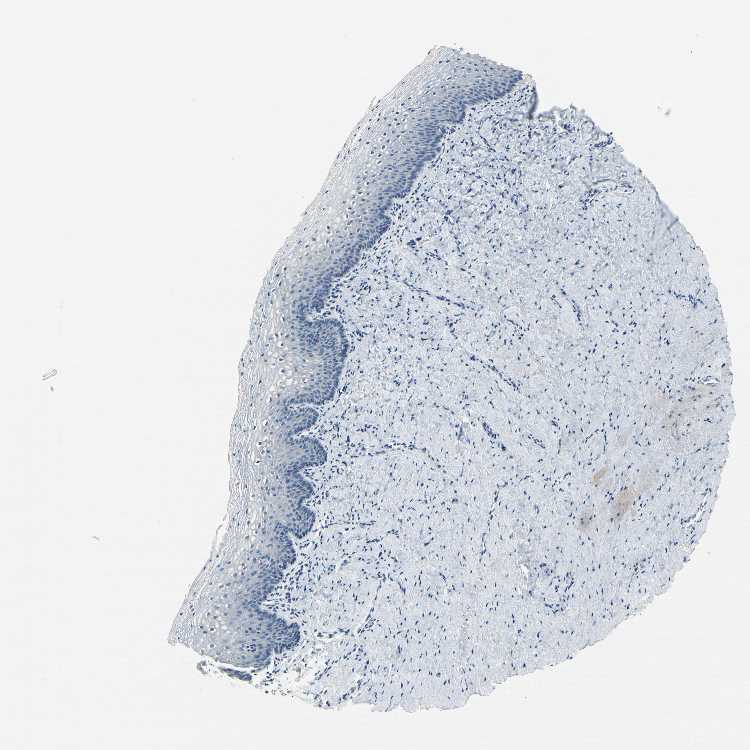

FCER2